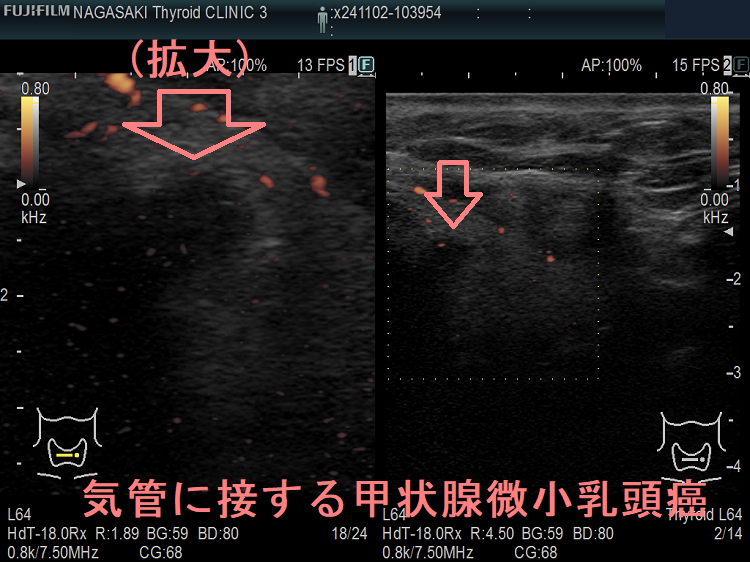

- 気管に浸潤している可能性がある[気管との間に被膜なく、鈍角で(アワビ状に)気管に接している]・甲状腺背面に鈍角で(アワビ状に)反回神経に接する7mm以上の甲状腺微小乳頭癌は、気道内への出血・反回神経麻痺の危険から、甲状腺を半分切除~全部摘出せねばなりません。(Thyroid. 2016 Jan 1; 26(1): 144–149.)(World J Surg 2016;40:523–528.)(下記)

隈病院でも、鈍角で(アワビ状に)気管に接する甲状腺微小乳頭癌(図のA)は、手術適応にしています(Thyroid. 2021 Feb;31(2):183-192.)

上のエコー画像は長崎甲状腺クリニック(大阪)の自験例です。気管に鈍角で(アワビ状に)接していませんが、拡大画像を見れば分かるように、明らかに甲状腺を包む被膜が消失し、気管に浸潤している様に見えます。